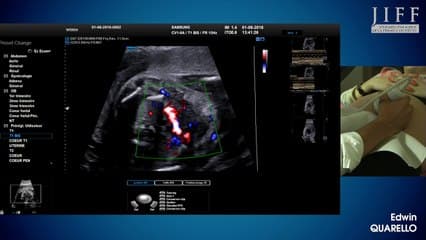

Vous y trouverez des conférences présentées lors des congrès nationaux et internationaux, des cours magistraux dispensés par des experts reconnus, des démonstrations pratiques sur des cas cliniques réels, ainsi que des podcasts et tables rondes sur les dernières avancées de la spécialité.